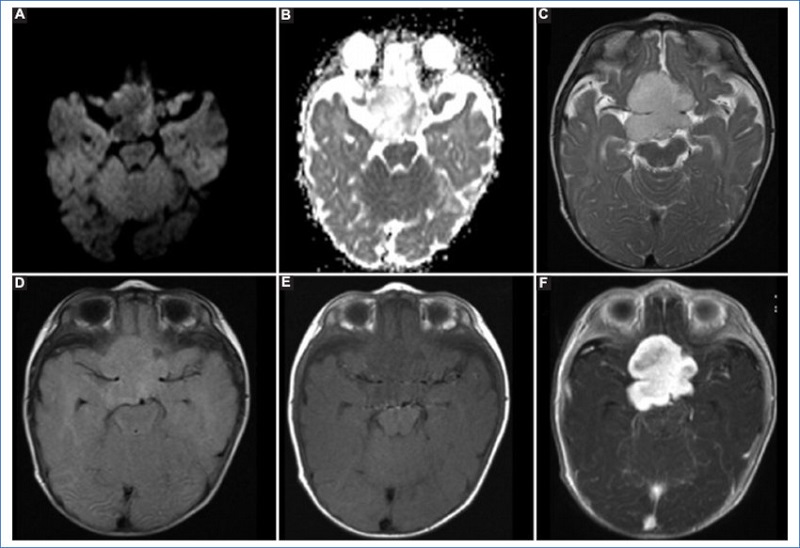

En cuanto a los tumores de origen glial, los más frecuentes en la población analizada fueron los astrocitomas, viéndose cuatro casos de bajo grado que comprendieron un astrocitoma pilomixoide, un astrocitoma óptico-quiasmático, un astrocitoma desmoplásico infantil y un astrocitoma gigantocelular. Los gliomas de bajo grado (grados 1 y 2) son los tumores del sistema nervioso central más frecuentes en pacientes pediátricos, representando el astrocitoma pilocítico el 15% de todos los tumores intracraneales pediátricos. En nuestro estudio se halló una variante de astrocitoma pilocítico, el astrocitoma pilomixoide, con una edad promedio de diagnóstico a los 18 meses y un comportamiento benigno en la RM, ya que se presentan como lesiones bien circunscritas, sin edema periférico ni infiltración parenquimatosa, y con un leve componente quístico y realce homogéneo tras la administración de contraste9; características que coinciden con nuestros hallazgos (Fig. 3). Si bien el tratamiento de elección es la resección quirúrgica, con pronóstico más favorable cuanto mayor es el volumen tumoral resecado, en nuestro paciente se realizó el procedimiento quirúrgico y falleció durante el mismo. En los otros tres casos de astrocitomas que observamos, las características radiológicas fueron similares: lesiones sin hemorragia y sin diseminación al momento del diagnóstico, con realce intermedio o nulo tras la administración de contraste intravenoso y con restricción variable en la secuencia de difusión. El paciente con astrocitoma óptico quiasmático recibió quimioterapia, con posterior progresión de la enfermedad y trastornos de la deglución como secuela en la actualidad. En el paciente con astrocitoma desmoplásico infantil se realizó resección parcial y en el paciente con astrocitoma gigantocelular se tomó una conducta expectante; ambos están sin secuelas actualmente.